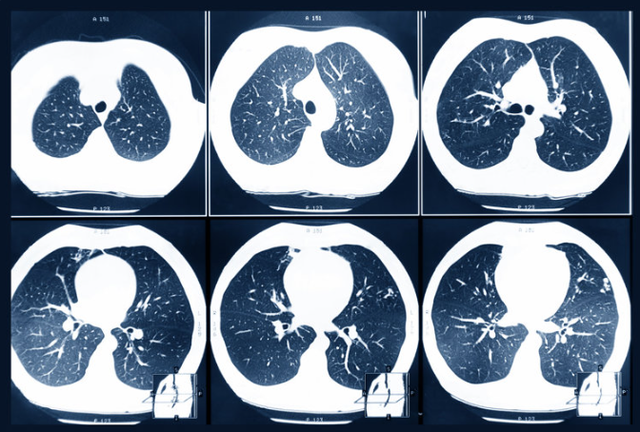

常规体检套餐通常只包含基础检查,而癌症的早期筛查需要更专业、更针对性的项目。比如,要发现早期肺癌,可能需要低剂量CT扫描;要筛查结直肠癌,可能需要结肠镜检查。